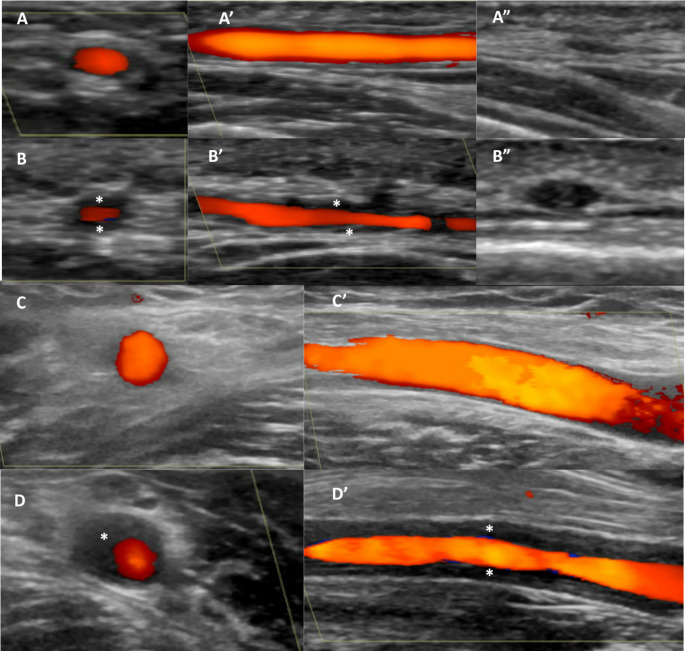

Abstract Image